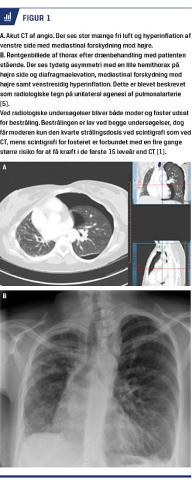

Biokemiske undersøgelser viste let forhøjede infektionstal med C-reaktivt proteinniveau på 13 mg/l, og D-dimer var forhøjet til 1,2 mgFEU/l uden kliniske tegn på dyb venetrombose. Der var A-gas med normal pH-værdi på 7,38, nedsat partialtryk af ilt på 8,8 kPa og normalt partialtryk af kuldioxid på 5,4 kPa. En ekkokardiografi viste normal pumpefunktion, ingen klap-patologi og perikardievæske samt vena cava inferior med respiratorisk kollaps. På mistanke om lungeemboli blev der foretaget CT, som ikke viste lungeembolier, men en stor mængde fri luft på venstre side med forskydning af mediastinum mod højre, hvilket radiologisk blev tolket som trykpneumothorax. Patienten blev behandlet med pleuradræn og blev udskrevet fem dage senere.

CT’en viste ingen tegn til lungeemboli, men overraskende manglende afgang af højre pulmonalarterie. Samtidige fund var hypoplastisk højre lunge og hyperplastisk venstre lunge, der strakte sig ind over midtlinjen. Forebyggende for recidiverende pneumothorax foretog man talkumpleurodese, og patienten fødte vaginalt og ukompliceret.

I litteraturen fremhæves to debutaldre, nemlig hos symptomatiske spædbørn og relativ asymptomatiske voksne. Tilstanden blev først beskrevet i 1868, og siden da er der i litteraturen beskrevet 419 tilfælde [5]. Højresidig UAPA forekommer hyppigst isoleret, mens venstresidig pulmonalarterieagenesi oftest forekommer i forbindelse med f.eks. Steno-Fallots tetralogi, atrie- og ventrikelseptumdefekter og coarctatio [5]. Ca. en fjerdedel af patienterne får pulmonal hypertension [4]. Diagnosen UAPA stilles ved grundig anamnese og billeddiagnostik såsom røntgen af thorax, ekkokardiografi, CT og MR-skanning [5] (Figur 1).